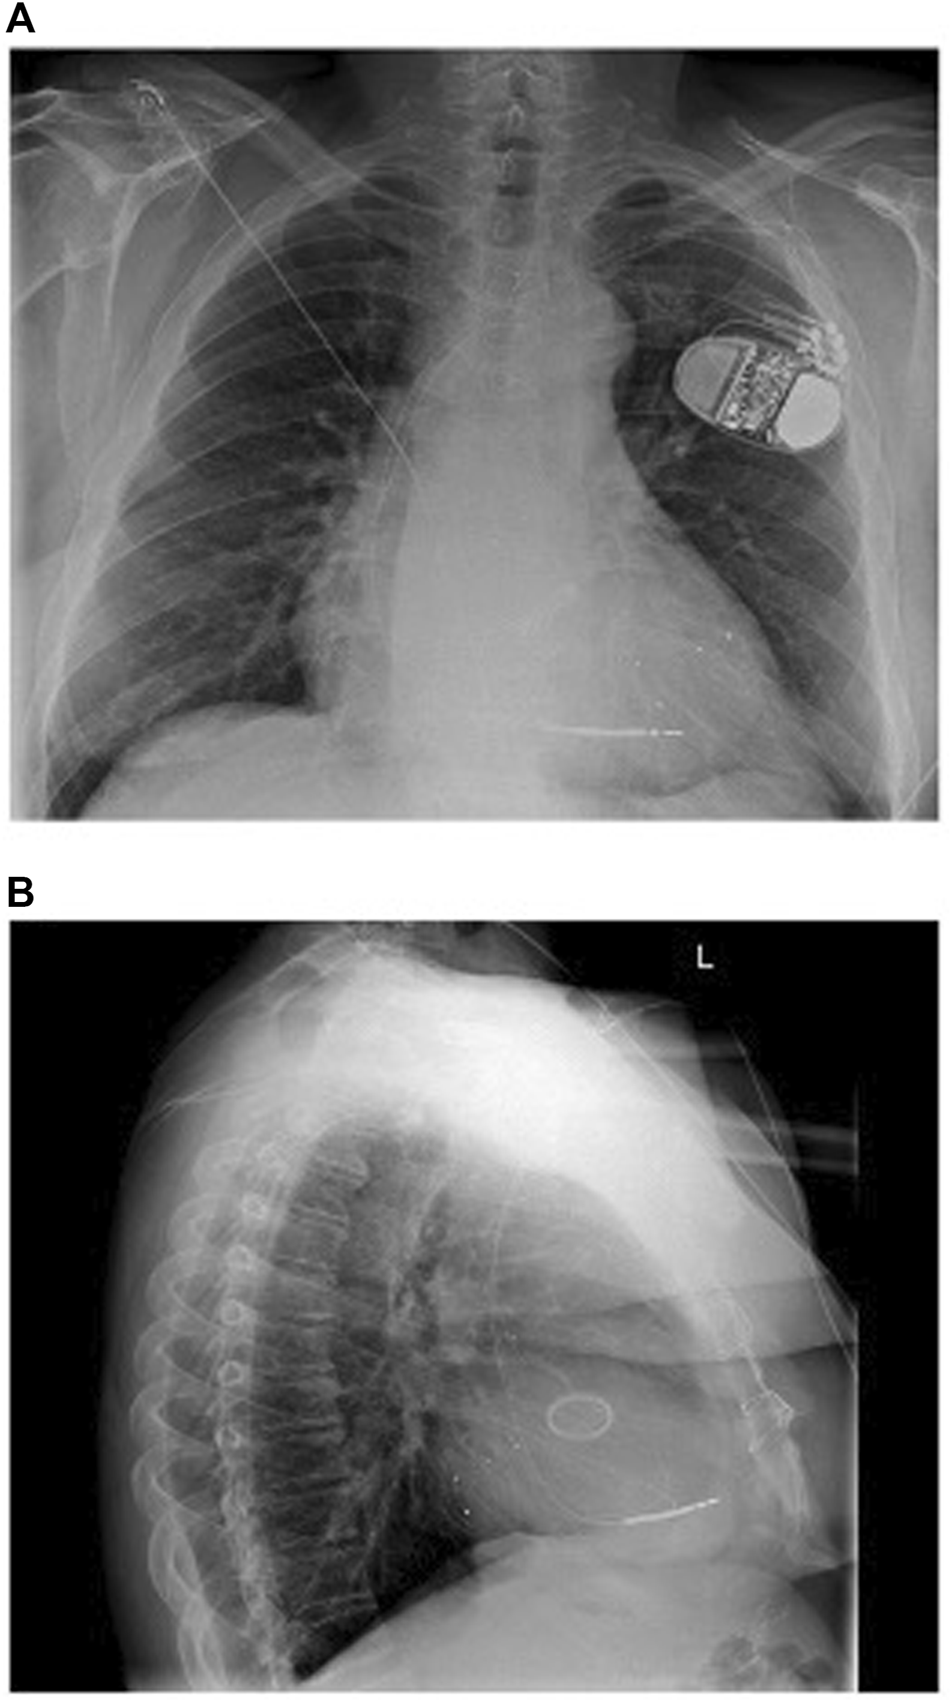

Multi-lead pacing, that is, the placement of an additional lead, most commonly in the LV to provide Triventricular (TriV) pacing (Figure 1), has also been evaluated in randomised control trials. The V3 trial (Bordachar et al., 2018) and STRIVE-CRT (Gould et al., 2022) are important negative trials which showed no significant difference in clinical or echocardiographic outcomes between standard of care and multi-lead pacing in unselected CRT populations. A meta-analysis of 415 patients by Elliott et al. (Elliott et al., 2022a) again reported no difference between TriV pacing and conventional BiV pacing.

FIGURE 1

(A) Anteroposterior and (B) Lateral chest radiograph views 1 day post implant of triventricular CRT system with one LV lead in posterolateral vein and another in a lateral vein. Reproduced from reference 23, Gould et al., with permission.